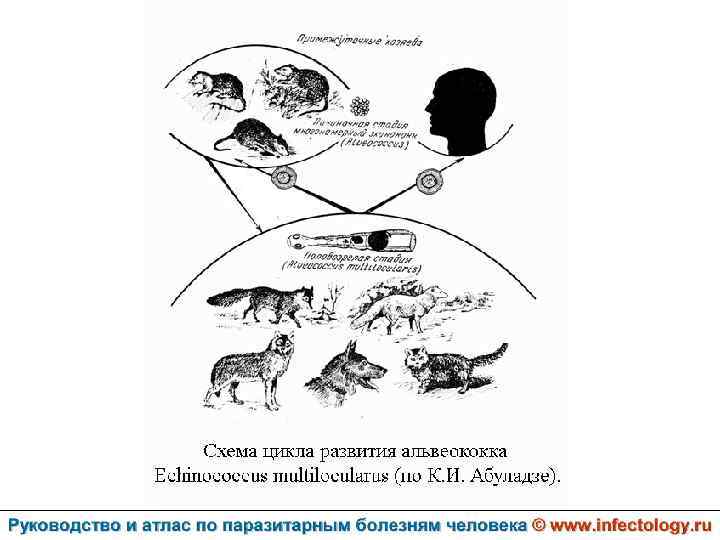

Альвеолярный (многокамерный) эхинококкоз человека (альвеолярный гидатидоз) (шифр по МКБ 10 - B 67. 5 -7) – зоонозный биогельминтоз, характеризующийся чрезвычайно тяжелым хроническим течением, первичным опухолевидным поражением печени, нередко с метастазами в головной мозг и легкие, а также во многие другие органы. Заболевание часто заканчивается летально.